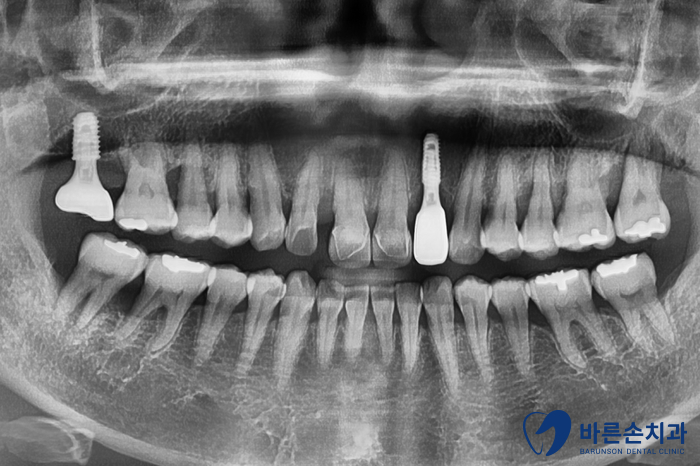

Before 25.05.08

보시면 앞니 하나가 유독 뼈가 내려가 있는 걸 볼 수 있어요.

치아를 잡아주는 뼈가 별로 없다보니

치아가 밑으로 내려오면서 많이 흔들리는 상태였습니다.ㅠㅠ